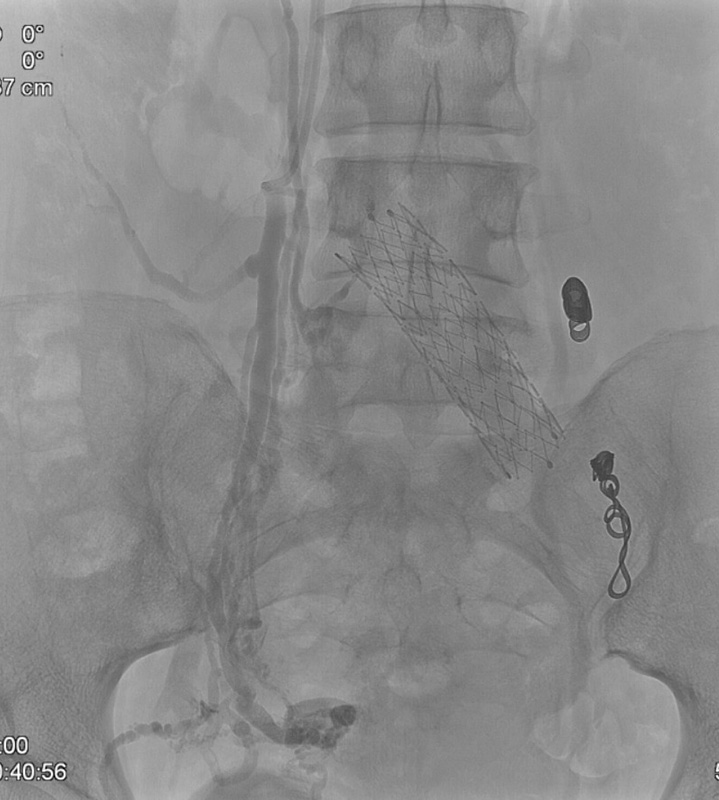

Примером лечения варикозной болезни малого таза в АО ЦЭЛТ может служить история болезни молодой женщины из Дагестана, которая обратилась к нам по поводу хронической тазовой боли. Она беспокоит ее уже несколько лет и существенно мешает жить. Длительное время пациентка лечилась у разных специалистов и уже перенесла стентирование левой подвздошной вены. Несмотря на проводимую терапию и хирургическое вмешательство, жалобы не проходили. После онлайн-консультации в сосудистом центре АО ЦЭЛТ, пациентка прилетела к нам для флебографии и эмболизации варикозно расширенных вен малого таза. Через прокол в вену предплечья мы установили специальный порт – интродьюсер – для проведения медицинских инструментов в сосудистое русло. Специальный изогнутый катетер по проводнику был заведен в правую и левую варикозно расширенные яичковые вены. Каждая вена была с признаками несостоятельности клапанов, а диаметр их превышал 12 мм (при норме 4-6). Поэтому, мы выполнили женщине дистально-проксимальную эмболизацию яичниковых вен кубитальным доступом. Операция была настолько малотравматична, что уже утром следующего дня больная смогла улететь домой.

На фотографиях видно, как варикозные вены сначала заполняются контрастным веществом, имитирующим кровь. После установки спиралей, такого контрастирования не отмечается.